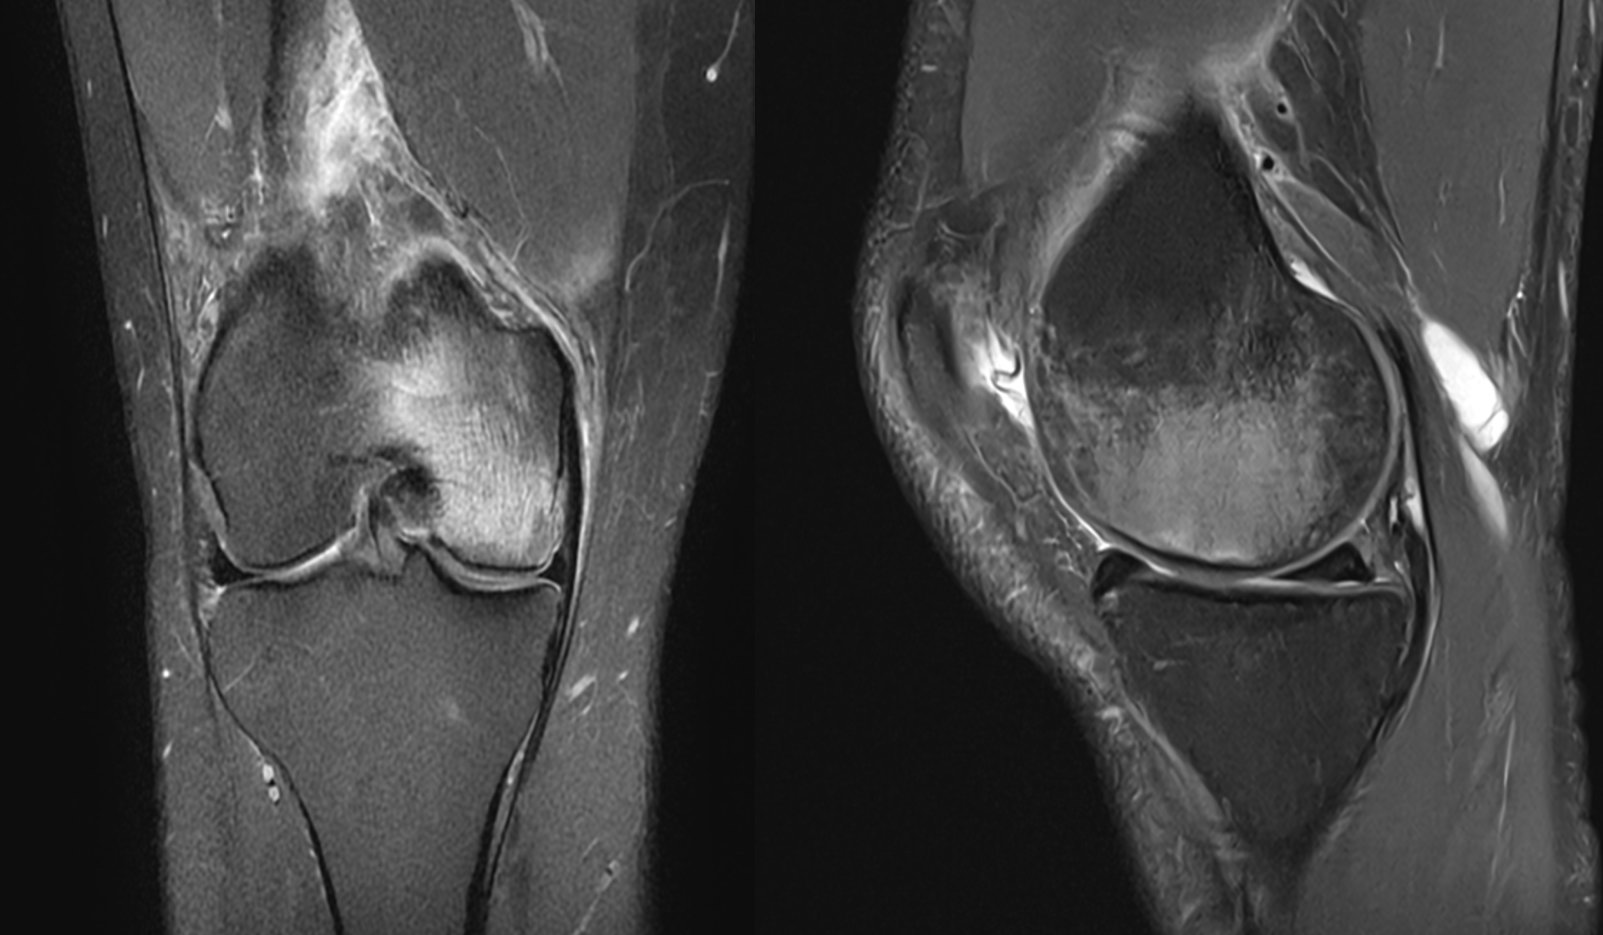

Rezonans magnetyczny (MRI) – jest badaniem z wyboru w diagnostyce SIFK. Badanie to pozwala postawić właściwą diagnozę. Charakterystyczne cechy to linia hipointensywna w sekwencji T2 w obszarze podchrzęstnym (odpowiadająca linii złamania) oraz rozległy obrzęk szpiku kostnego. MRI umożliwia również ocenę towarzyszących uszkodzeń łąkotek i chrząstki.